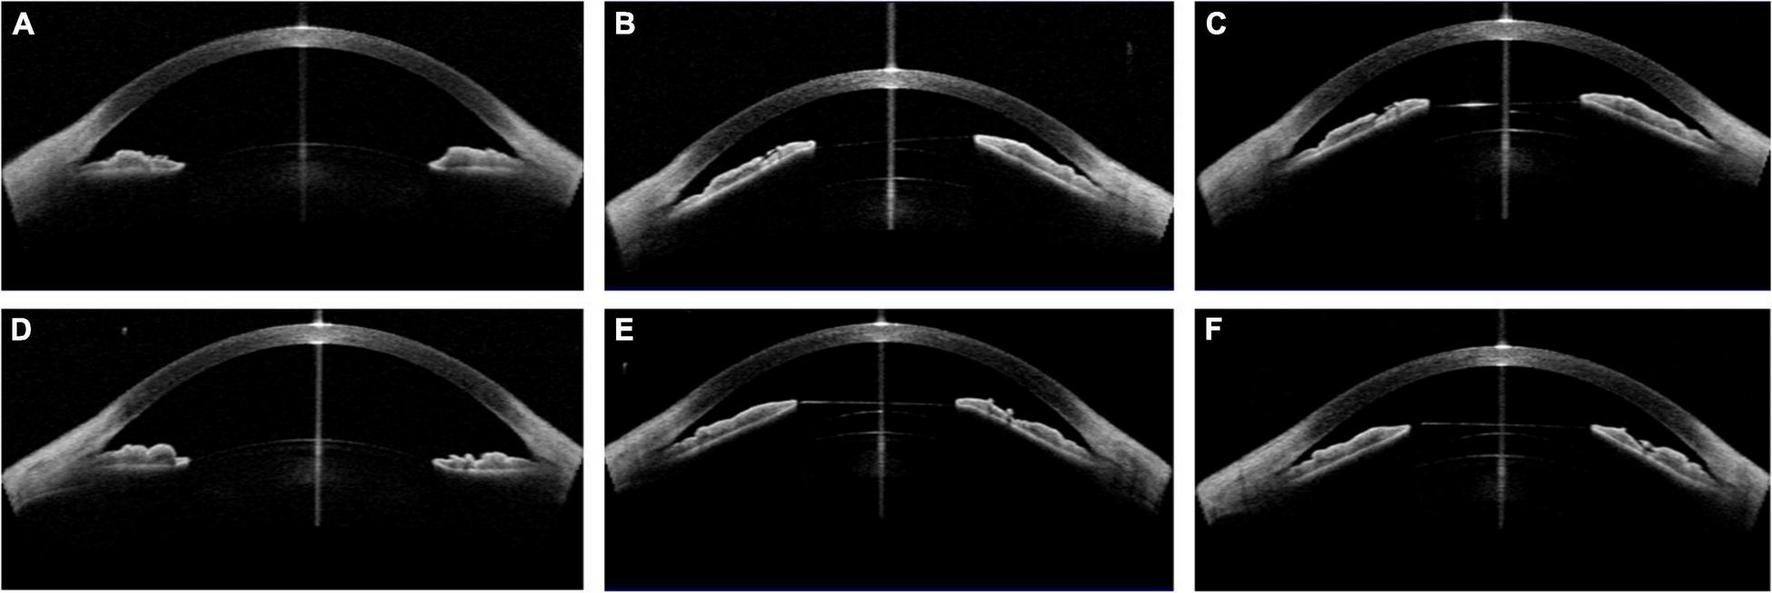

Case 3: (A,D) Concave shape iris before surgery; (B) low vault was shown 1 day postoperatively with 121 ICL; (C) the vault was slightly increased after ICL exchange into 126 ICL 1 month postoperatively; (E) the vault of the left eye was larger than that of the right eye with 126 ICL; (F) the vault decreased 1 month postoperatively. (Row 1: right eye; Row 2: left eye).